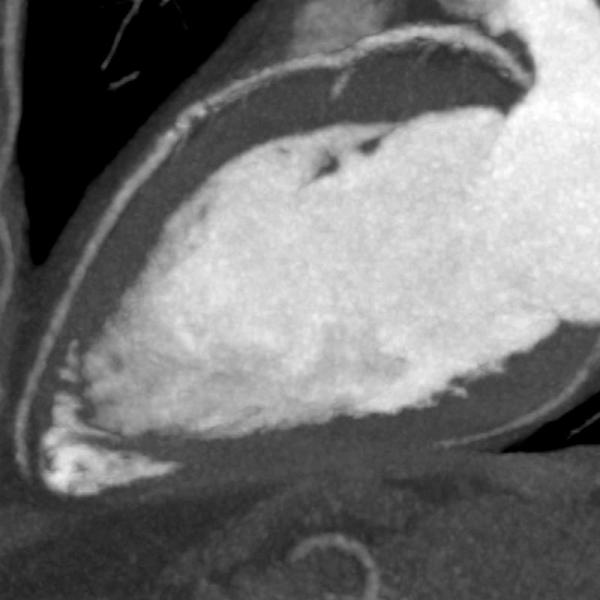

Severe coronary calcification influences the effectiveness of coronary CTA in ruling out CAD. Frequently these patients are referred for invasive angiography because of clinical suspicion of significant CAD. Stents placed in the coronary arteries can make visualization of the lumen within the stent difficult, hindering the ability to diagnose in-stent restenosis. SURE Subtraction Coronary removes calcification and stents from the coronary arteries, therefore improving visualization of the coronary lumen. Blooming effects caused by calcification are dramatically reduced.

An added benefit of SURE Subtraction Coronary is that it can be obtained with a near-dose-neutral scanning protocol. Coronary Subtraction is performed by subtracting a routine calcium score dataset from a coronary CTA dataset, the calcium score scan being used as the non-contrast mask for subtraction. Atlas-based cardiac segmentation and sophisticated rigid and deformable registration algorithms enable accurate subtraction of the coronary arteries to become a reality, leading to improved visualization of the coronary lumen.